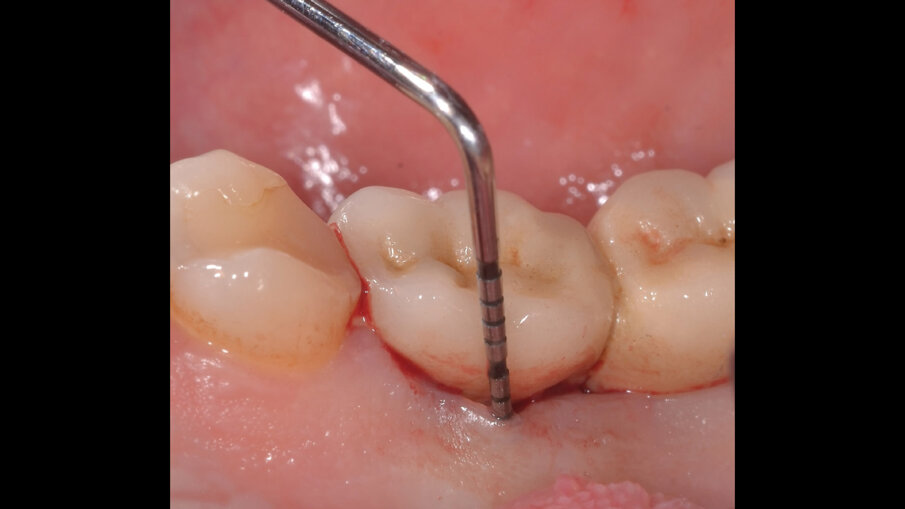

Il paziente, di sesso maschile e di 48 anni di età, è in buone condizioni di salute generale ma, a distanza di 10 anni dall’inserimento, presenta due impianti endossei, in posizione 4.6 e 4.7 con uniforme perdita ossea e con sondaggi di profondità variabile tra 6 e 9 mm accompagnati da sanguinamento, con tessuti marginali che mostrano importanti aspetti infiammatori, causa di sintomatologia dolorosa per il paziente (Figg. 1a-f).

I siti interessati sono stati strumentati per via non chirurgica, utilizzando strumenti manuali, strumenti ultrasonici e air polishing con eritritolo. Al termine della seduta è stato applicato il gel di ozono (Ozosan Gel - Bioactiva) all’interno delle tasche, lasciando agire il dispositivo per 8 minuti, quindi eseguendo lavaggio con soluzione fisiologica. Il post-operatorio ha avuto un decorso privo di dolore con rapida remissione della sintomatologia soggettiva. Il paziente è stato inserito in un programma di mantenimento parodontale trimestrale. A distanza di 6 mesi dal trattamento non chirurgico della perimplantite, i siti si presentano stabili con profondità di sondaggio ridotta tra i 3 e i 5 mm con assenza completa di sanguinamento al sondaggio (Figg. 1g-m).